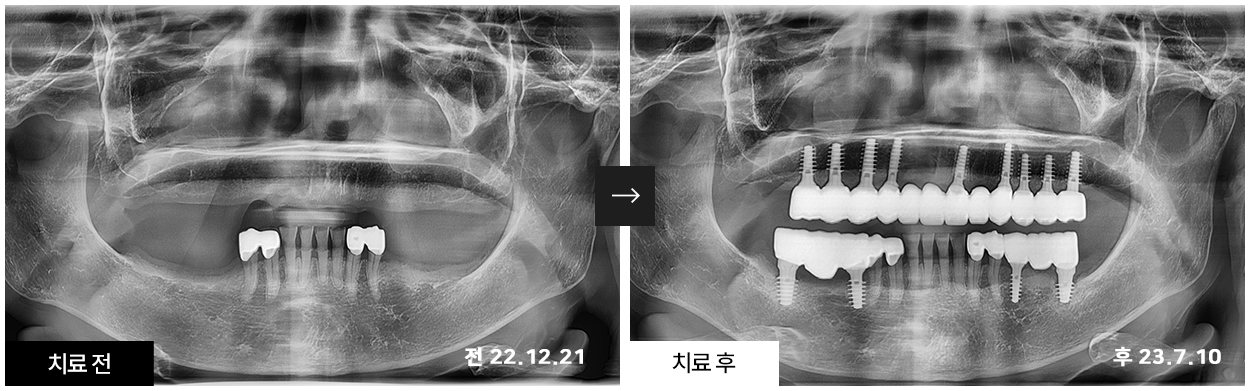

서울 0.1치과에서 치료받으신 환자분들의

치료 전/후 비교사진입니다.